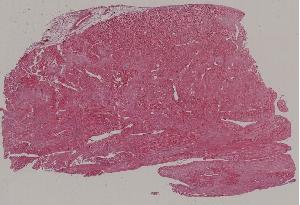

48. Viral myocarditis